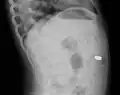

AP X ray showing a 9mm battery in the intestines

Lateral X ray showing a 9mm battery in the intestines